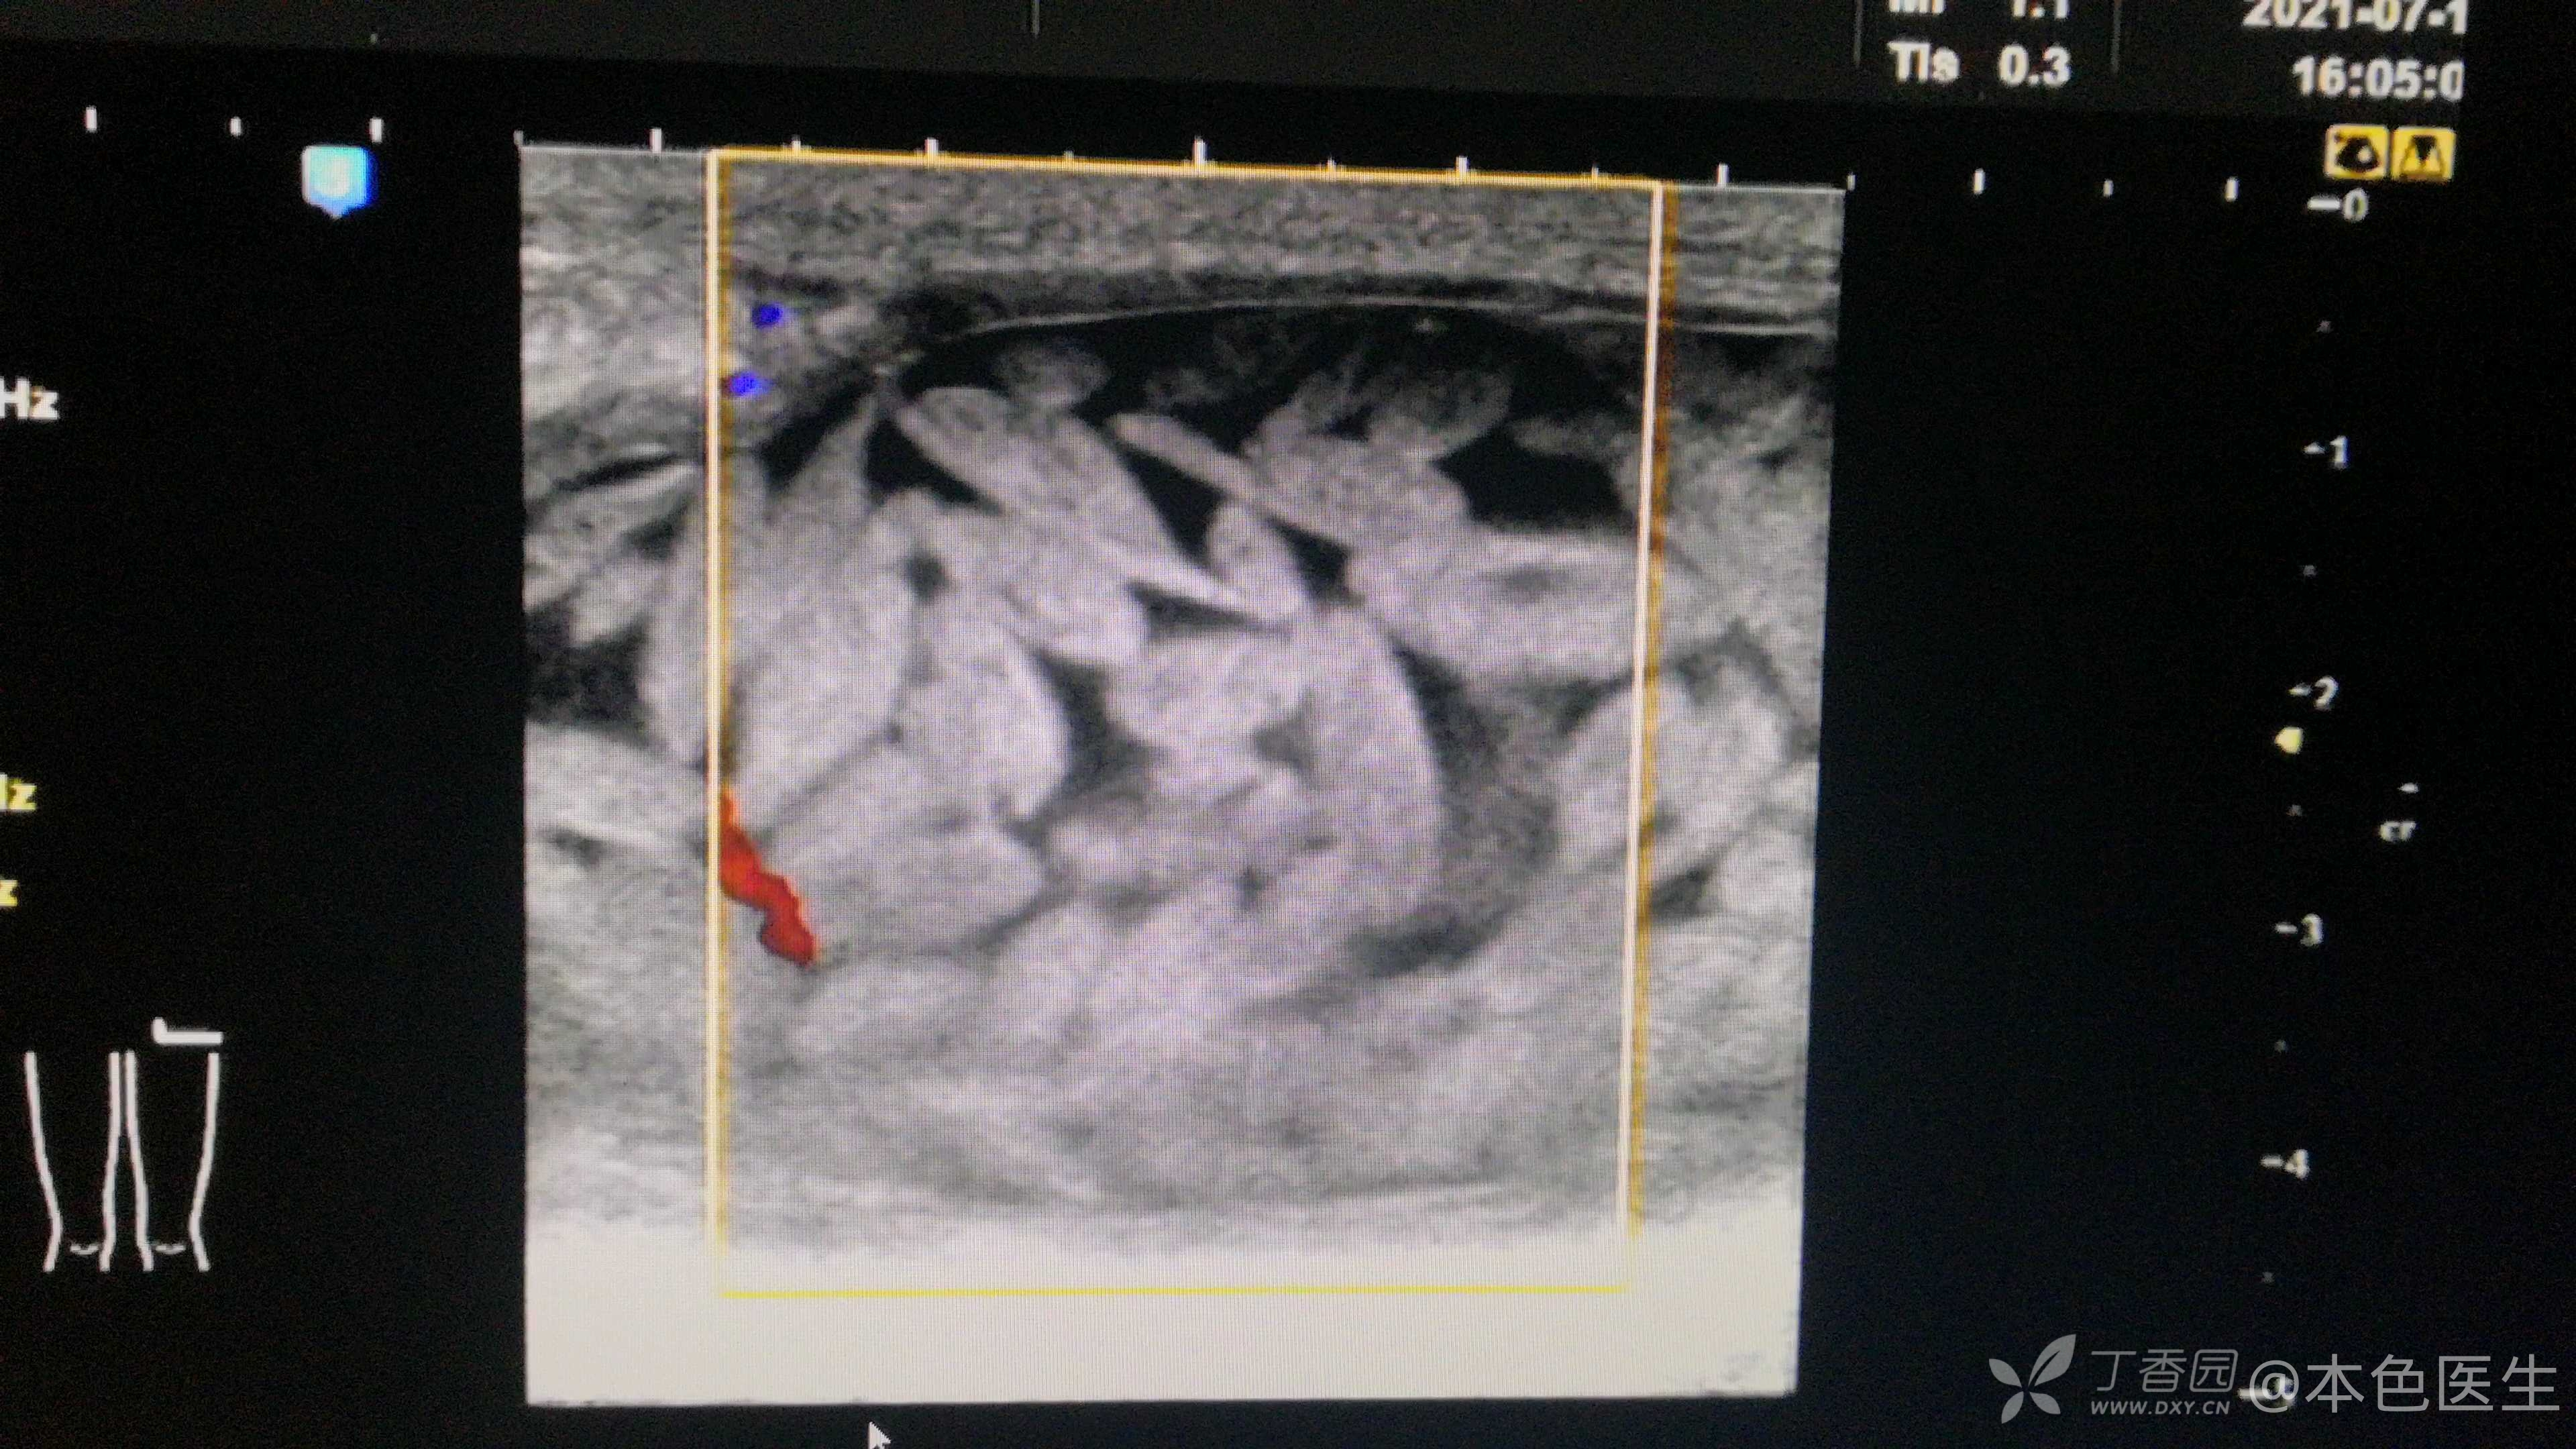

老年女性 88岁

病史和体征:右臀部包块伴局部伤口反复渗液11月。

右坐骨结节处皮肤陈旧性疤痕,局部包块大小约3x2x5cm,局部皮肤可见直径月5mm破溃口,按压有渗液。